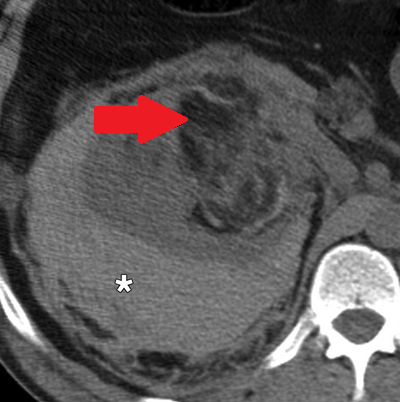

Αριστερό περινεφρικό αιμάτωμα και δεξιό αιμάτωμα λαγονοψοΐτη — αντιπηκτική αγωγή (Ευγενική παραχώρηση Dr. V. Penopoulos)